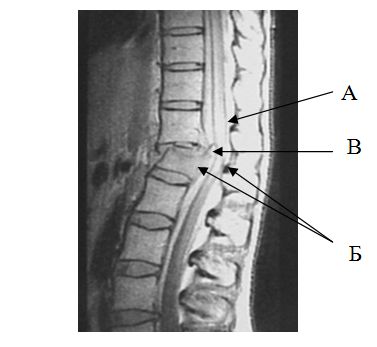

Для взрывных переломов тел позвонков с неврологическими нарушениями характерно наличие сужения позвоночного канала отломками тела позвонка, которые приводят к компрессии и сдавлению спинного мозга и его элементов, и возможное повреждение дискового аппарата. При взрывных переломах на МРТ имеются признаки ушиба спинного мозга в зоне повреждения, что выражается в картине его отека и появления участков изменения сигнала в местах кровоизлияния. Контур переднего отдела субарахноидального пространства при этом значительно сужается или исчезает полностью (рис. 7).

|

Рис. 7. МРТ признаки взрывного перелома

А – участок “свечения” в зоне ушиба спинного мозга; Б - деформация и стеноз позвоночного канала; В – сужение субарахноидального пространства |